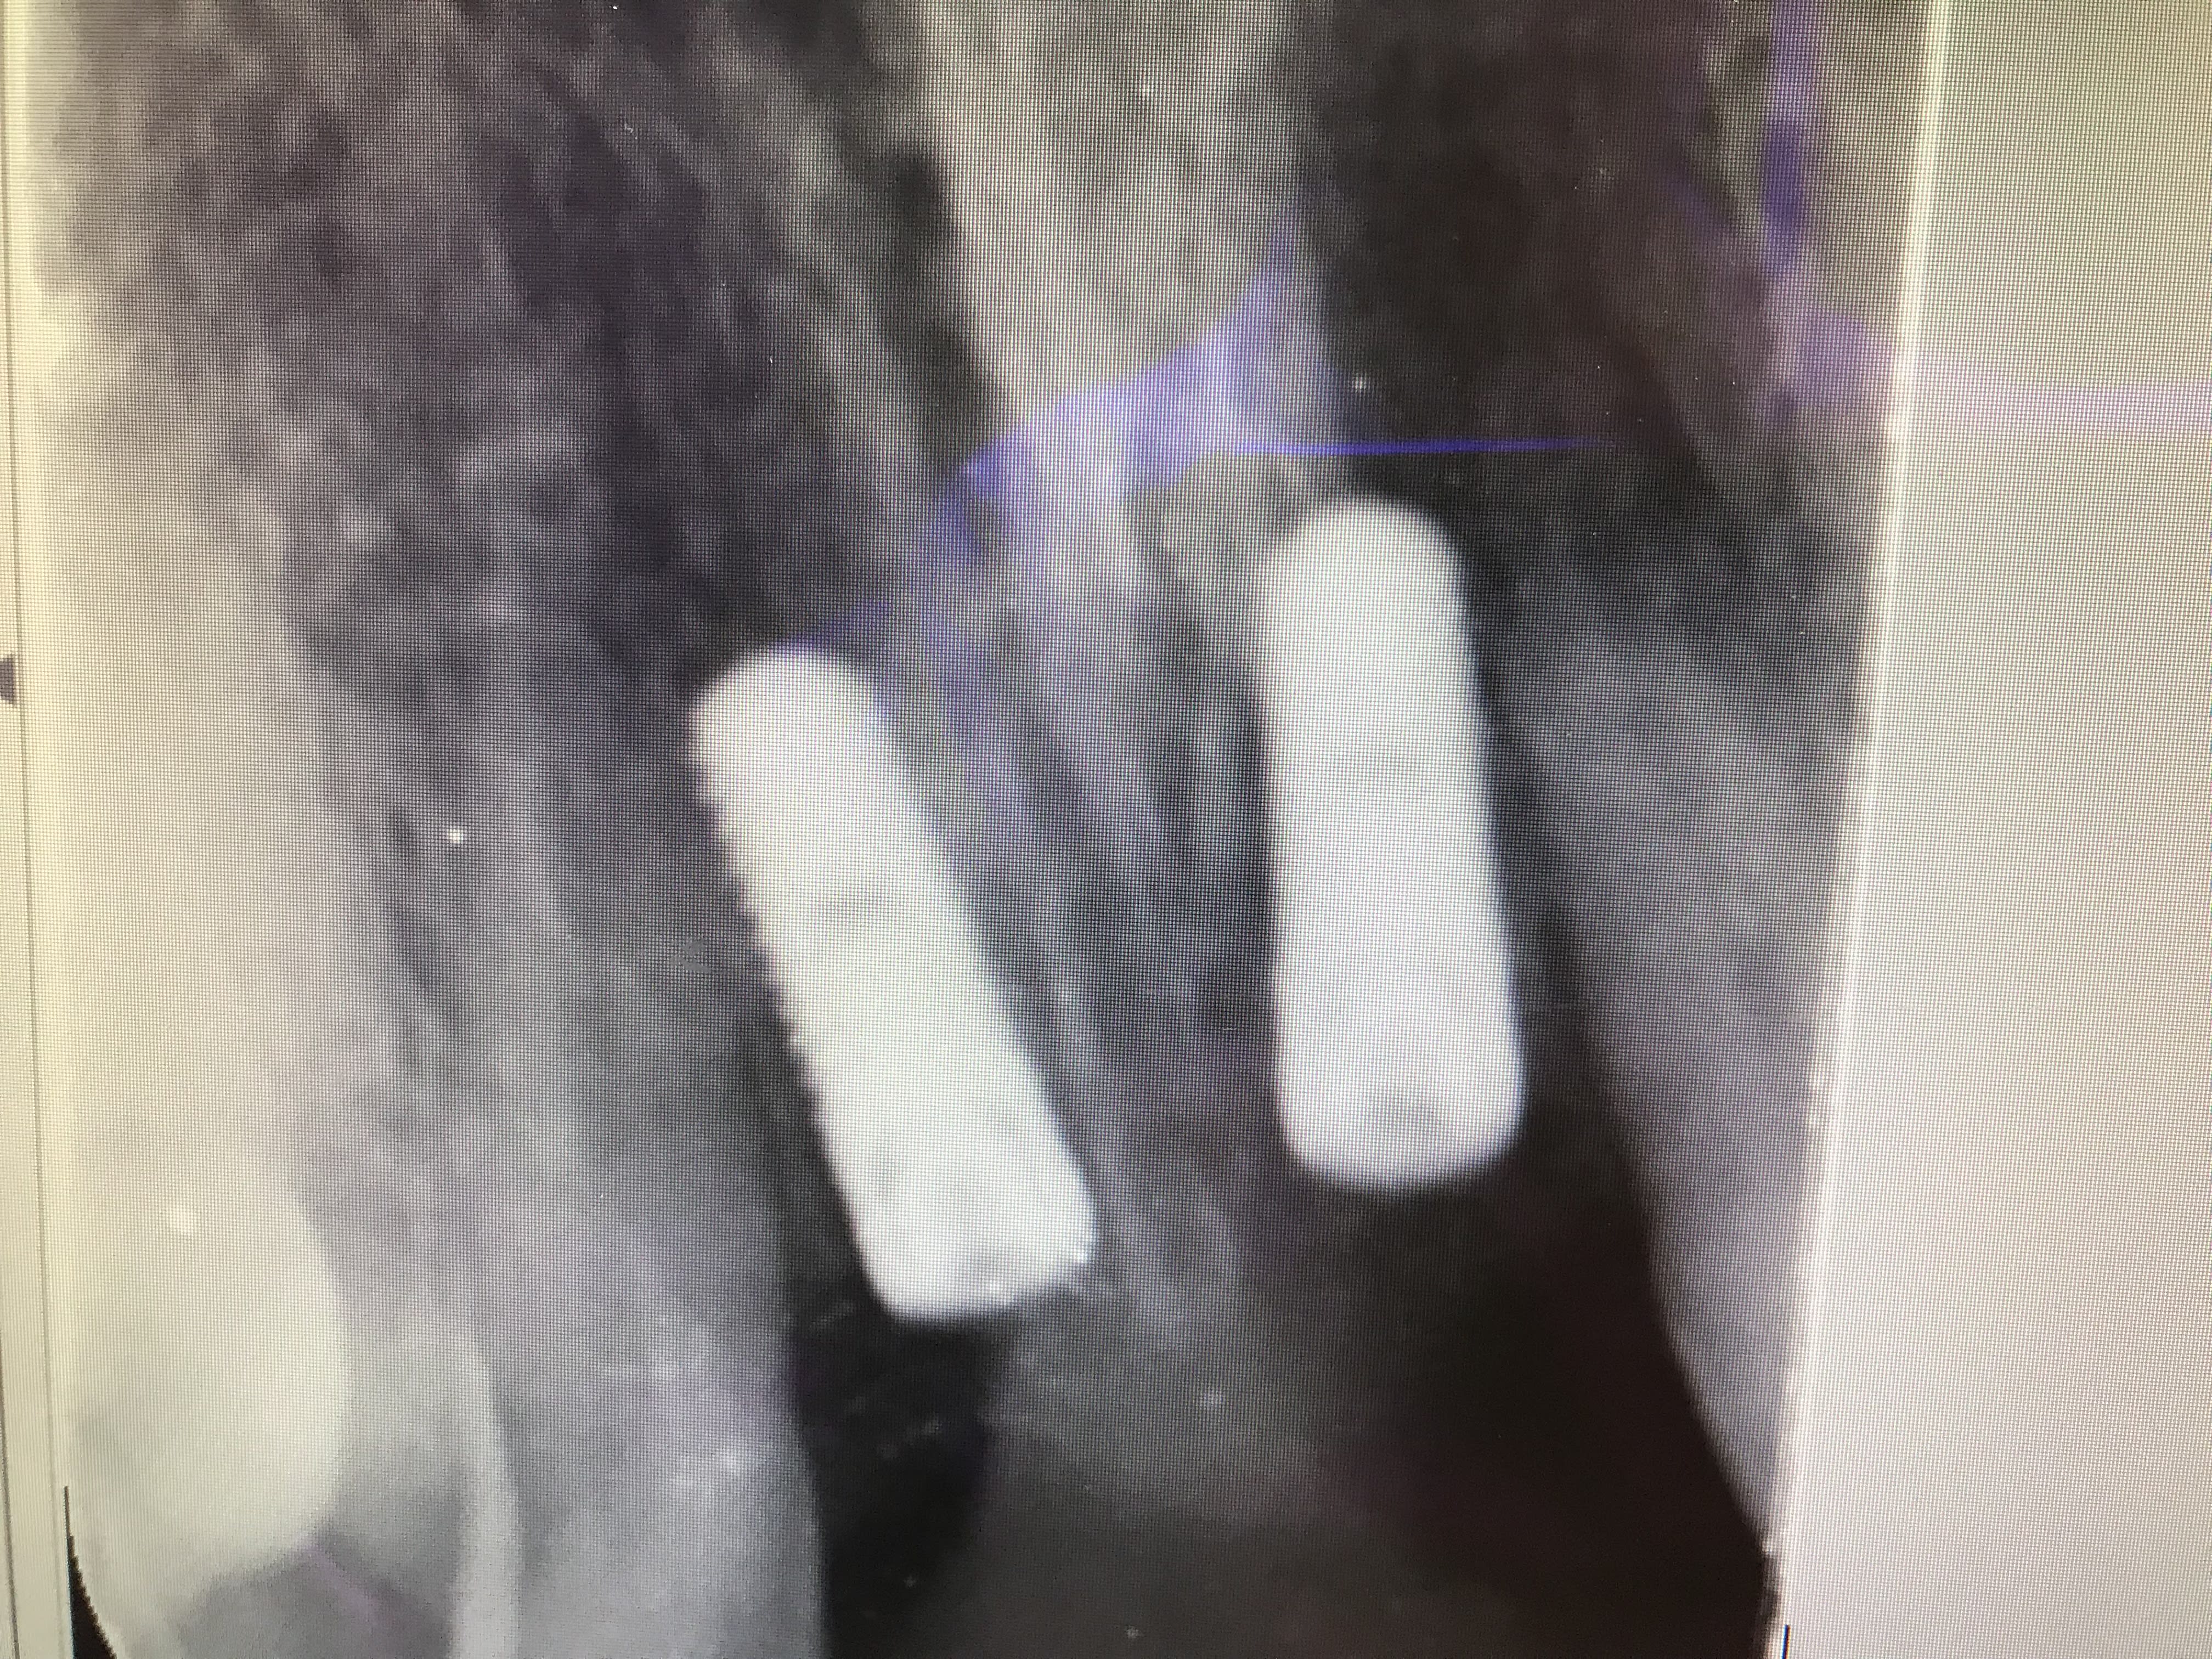

J’ai trouvé une indication réelle à l’ERI , c’est la lésion logée entre les racines . Ici pas de possibilité de faire de la résection. Imaginons que le traitement endo n’a pas d’effet => ERI

F87303d5 46d9 4260 8576 1ea51f30c09a noipel - Eugenol

Ylfwcw979cz1jnx9gfqeaxndiuzk - Eugenol